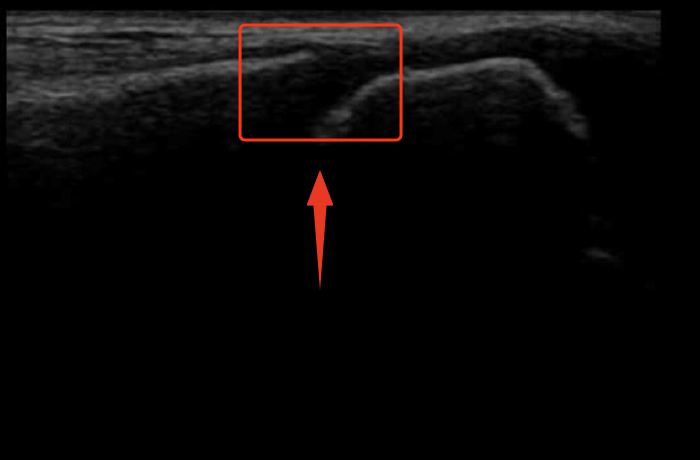

② ラストスパート時期

この時期になると、骨端線はまだ開いているものの、少しずつ閉じ始めてきている状態です。

成長のピークを過ぎ、伸びるスピードは緩やかになるものの、ここからさらに数cm程度伸びることが期待できます。思春期の後半に見られることが多いです。